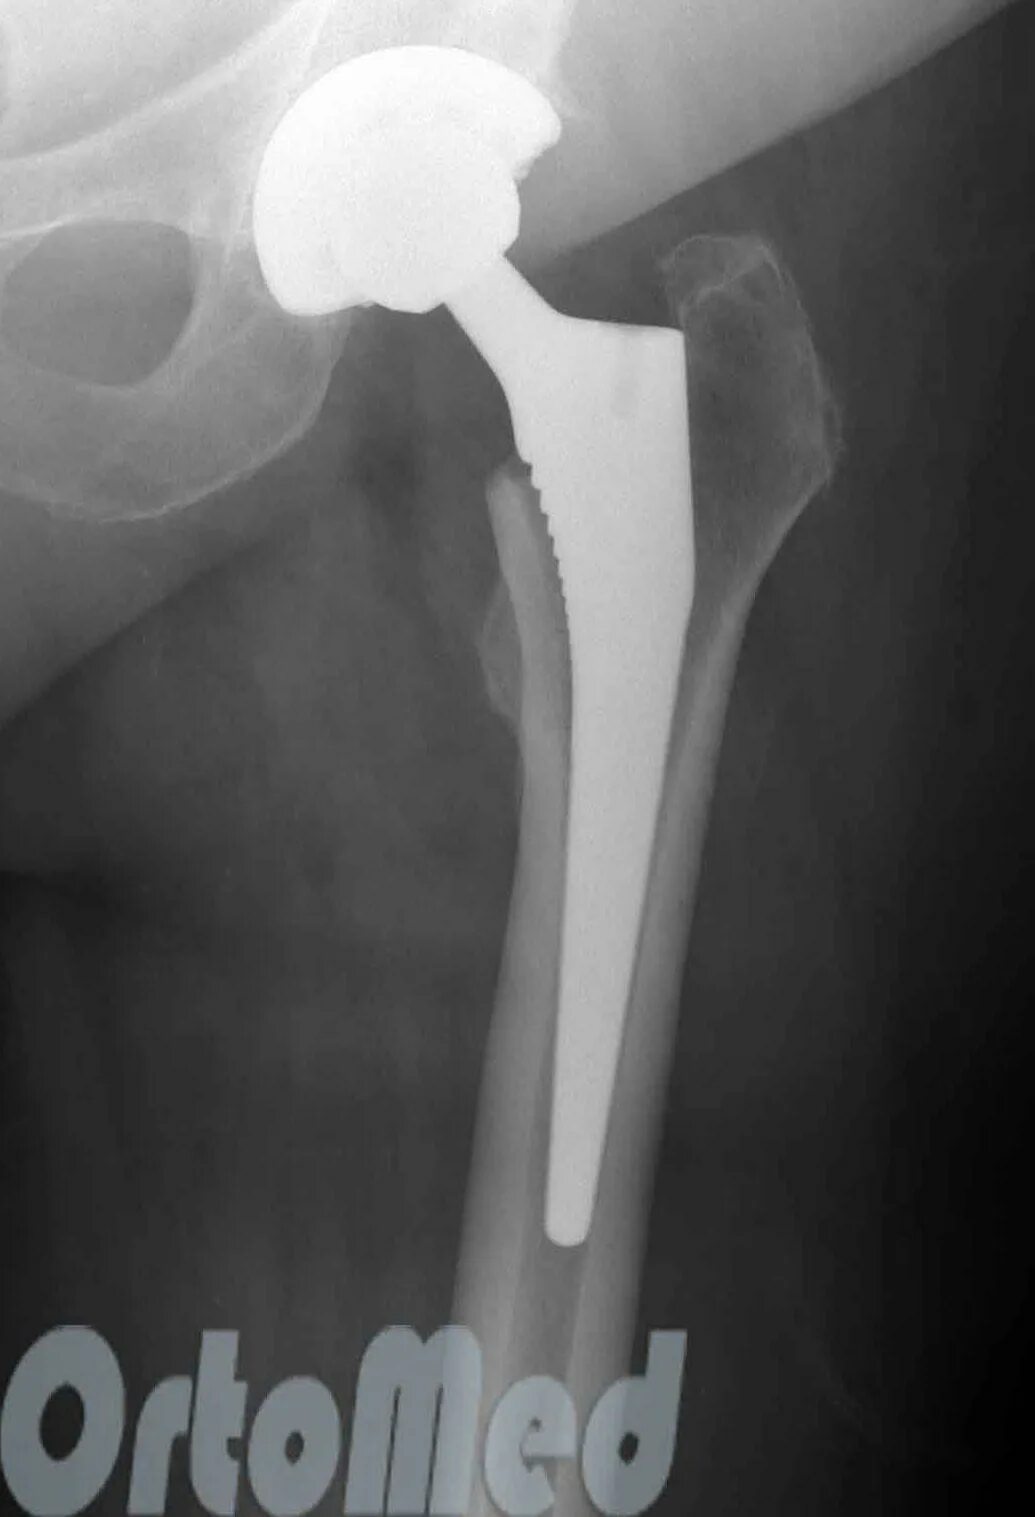

Срок службы тазобедренного эндопротеза